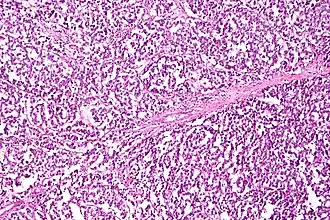

Granulosa cell tumor

Granulosa cell tumors are the most common sex-cord stromal tumors, making up 70% of cases, and are divided into two histologic subtypes: adult granulosa cell tumors, which develop in women over 50, and juvenile granulosa tumors, which develop before puberty or before the age of 30. Both develop in the ovarian follicle from a population of cells that surrounds germinal cells.[32]

Adult granulosa cell tumor

Adult granulosa cell tumors are characterized by later onset (30+ years, 50 on average). These tumors produce high levels of estrogen, which causes its characteristic symptoms: menometrorrhagia; endometrial hyperplasia; tender, enlarged breasts; postmenopausal bleeding; and secondary amenorrhea. The mass of the tumor can cause other symptoms, including abdominal pain and distension, or symptoms similar to an ectopic pregnancy if the tumor bleeds and ruptures.[32]